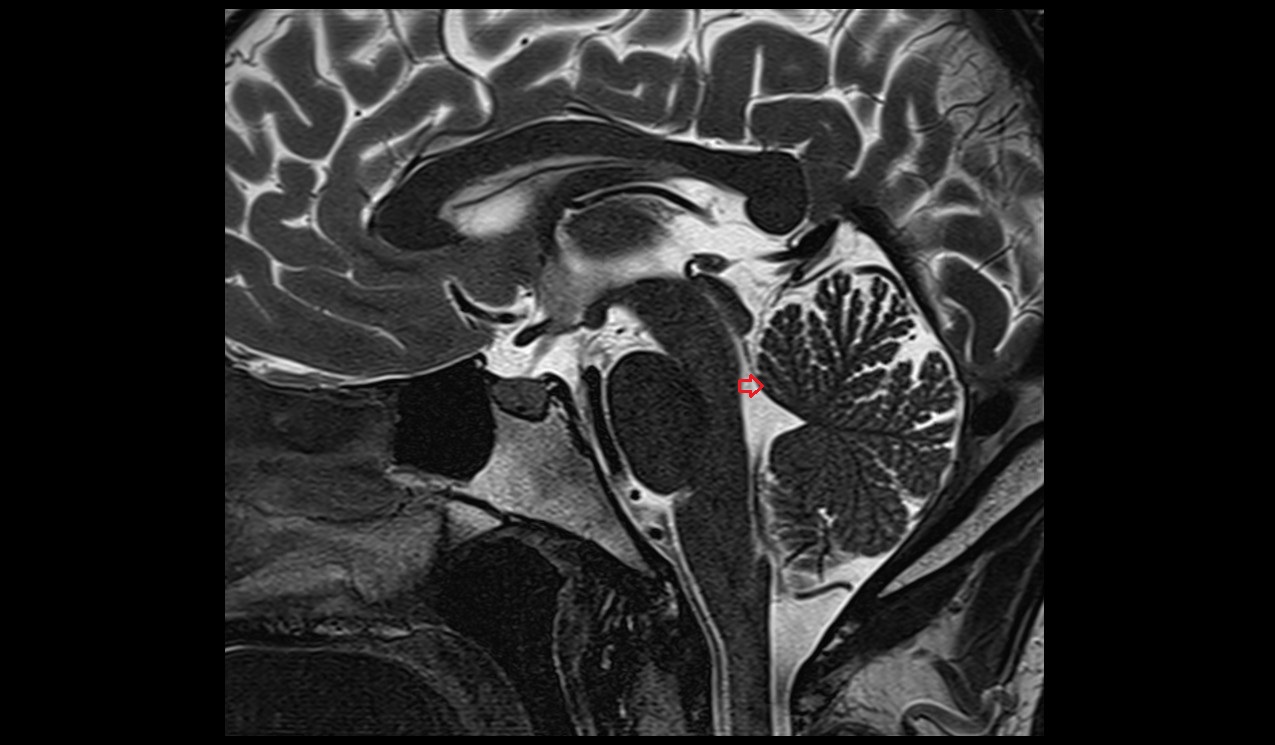

- Cerebral aqueduct

- Median aperture of fourth ventricle (foramen of Magendie)

- Cisterna magna

- Aqueduct of midbrain (Sylvian Aqueduct)